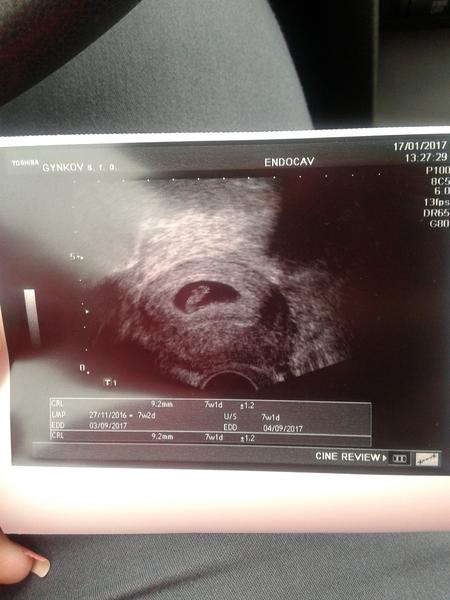

trrr tak jsem volala k dr. a hcg 3000,ale pirad mi tvrdi, ze to muze byt mimodelozni, tak v pondělí na kontrolu znovu na UTZ jestli uz tam neco bude.. Chjo, ta nejistota 😓